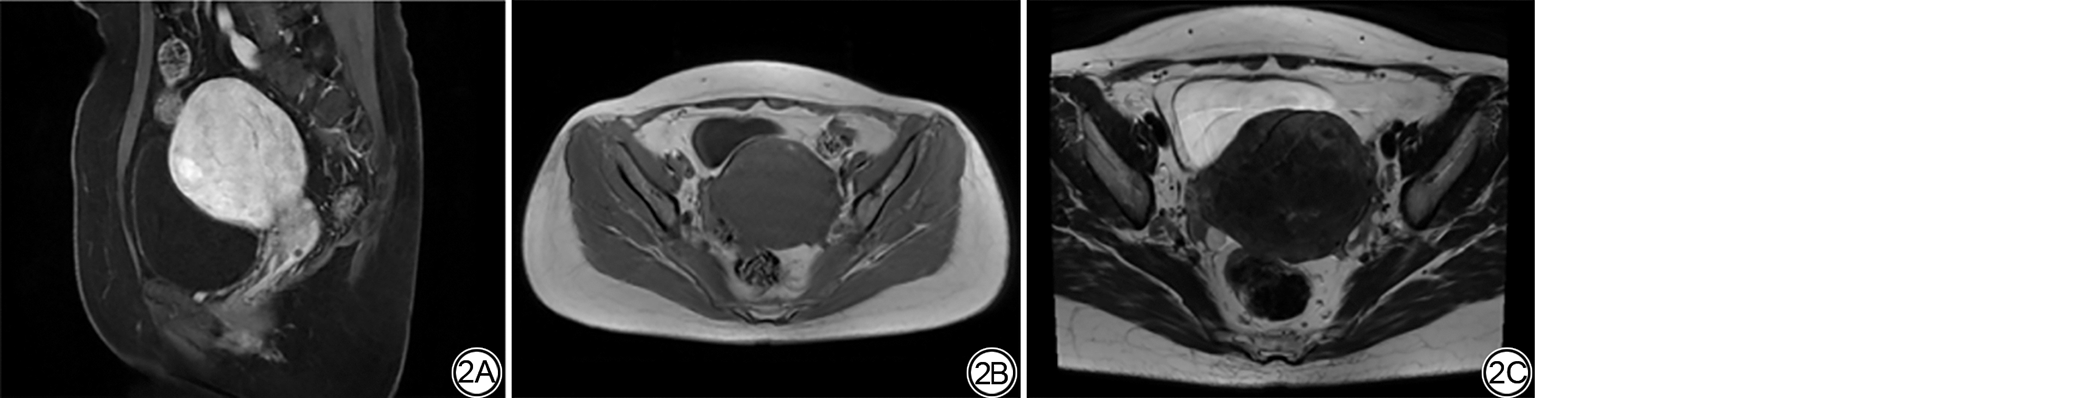

图4  女,48岁,子宫腺肌病患者高强度聚焦超声(HIFU)消融效果不佳。4A:T2WI病灶内呈混杂低信号;4B:纤维示踪图显示病灶区域纤维示踪中断,纤维形态杂乱,纤维束密度为10.33,预测HIFU消融效果不佳;4C、4D:HIFU术后T2WI、弥散张量成像纤维示踪图像,非灌注体积比(NPVR)为34.21%,实际消融效果不佳,与预测相符合。

Fig. 4  Female, 48-year-old, patient with adenomyosis have poor high intensity focused ultrasound (HIFU) ablation efficacy. 4A: The adenomyosis lesion exhibits mixed hypointense signal on T2WI, which may indicate a higher degree of fibrosis; 4B: Fiber tractography shows interrupted and disorganized fiber structures within the lesion area; 4C, 4D: Post high intensity focused ultrasound T2WI and DTI tractography, the non-perfused volume ratio (NPVR) is 34.21%, indicating suboptimal ablation efficacy.

本研究中HIFU术后NPVR与术前病灶区域纤维束密度正相关。纤维束密度可评估组织微结构完整性。其反映了单位体积内纤维束数量、分布情况。纤维束密度高提示组织微结构纤维排列密集,纤维束密度低则提示纤维束排列松散,方向性丧失[32, 33]。由于子宫腺肌病病灶区域的平滑肌细胞大量增生,表现出轻中度纤维化。利于HIFU治疗的声能在上述区域内更快聚集,防止了一部分能量弥散或者过早衰减。且平滑肌增生纤维化区域内部的水分子含量相对较少,利于声能转化为热能,从而使得病灶部分产生凝固性坏死。另外,当病灶区域纤维化程度较高,排列紊乱,病灶结构不均匀时会导致纤维示踪中断,重建得到纤维束密度下降。因在HIFU治疗中组织大量纤维化可能导致超声能量的反射或衰减,不利于目标组织发生凝固性坏死。在本研究中当子宫腺肌病患者病灶部分在T2WI上表现为混杂极低信号时,在纤维示踪重建中可以看到重建图像中纤维束数量减少、中断,纤维密度较低,治疗效果不佳。